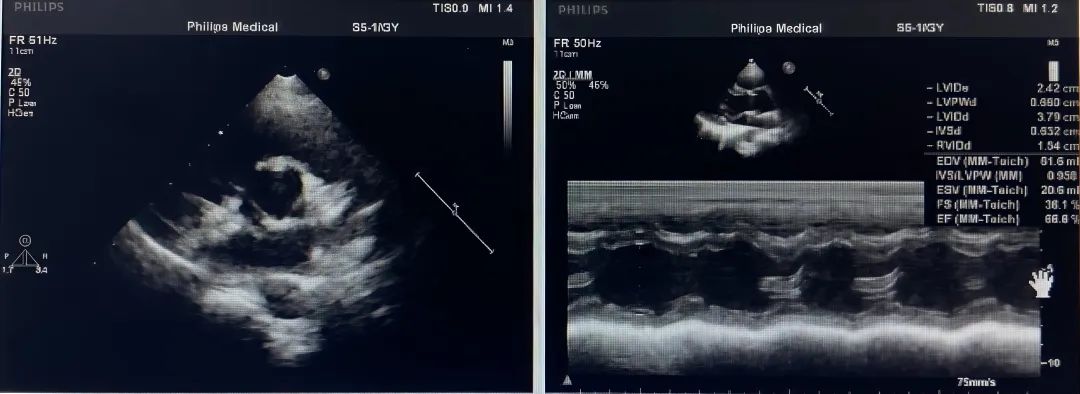

超声描述: